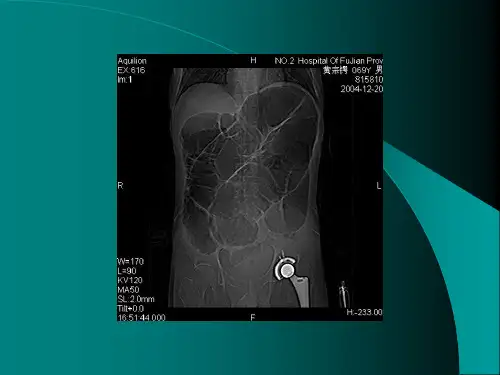

四、血管评估:

1.评估颈内动脉、基底动脉、前、中、后大脑动脉等血管的通畅程度和是否存在狭窄、扩张等异常。

2.提供血管造影图像,以便进一步评估血管结构。